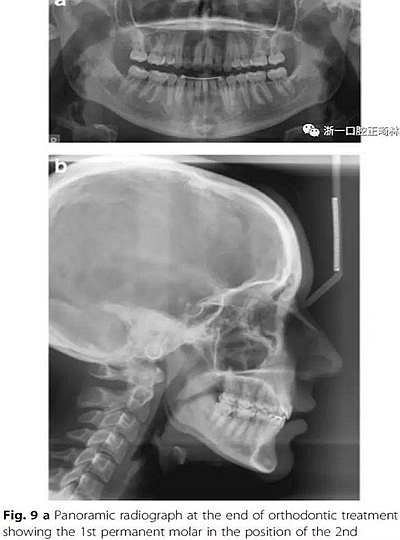

治療結(jié)果

雙側(cè)I類尖牙和磨牙關(guān)系;完全的間隙關(guān)閉(用牙線確定);覆合覆蓋糾正;仍有輕度的中線偏離。頭測分析顯示,下切牙未發(fā)生舌側(cè)移動。